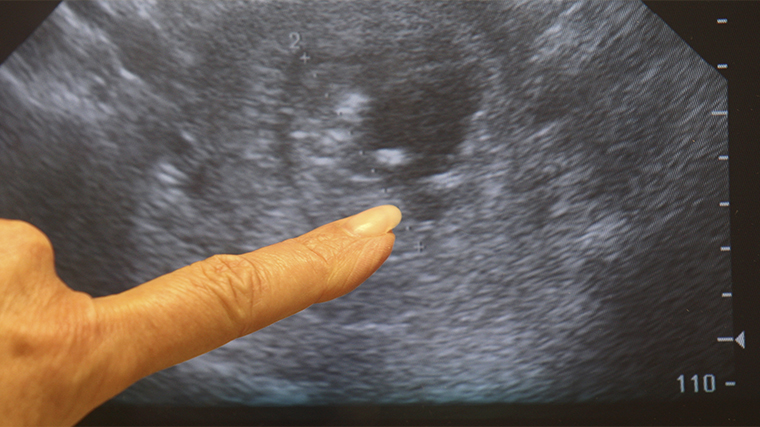

«Золотым стандартом» является анализ на хорионический гонадотропин человека (ХГЧ). Он может быть в виде обычного аптечного теста, либо вы также можете сдать анализ крови на ХГЧ. И также к достоверным методам обследования является УЗИ малого таза, подчеркивает эксперт.

УЗИ же не только подтверждает наличие плодного яйца, но и позволяет оценить его расположение, исключая внематочную беременность.

Ранняя постановка на учет позволяет своевременно выявить возможные риски, получить рекомендации по питанию и образу жизни, а также провести первое УЗИ, которое подтвердит, что плодное яйцо находится в матке и развивается правильно.

Важно помнить, что даже если тест оказался положительным, а УЗИ пока не проводилось, врач уже на раннем сроке может оценить состояние слизистой матки, исключить внематочную беременность и дать рекомендации по дальнейшему ведению беременности.